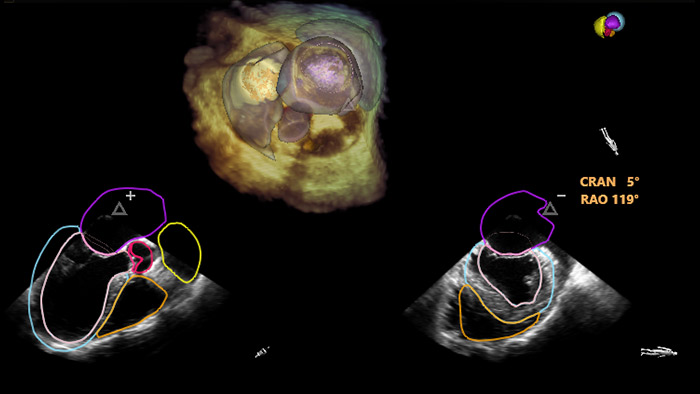

Segmentación del modelo EchoNavigator 3D

Optimización de la vista de la válvula mitral con modelos de corazón EchoNavigator

Optimización de la vista de la válvula tricúspide con modelos de corazón EchoNavigator

Visualización de las válvulas mitral y aórtica con modelos cardíacos EchoNavigator